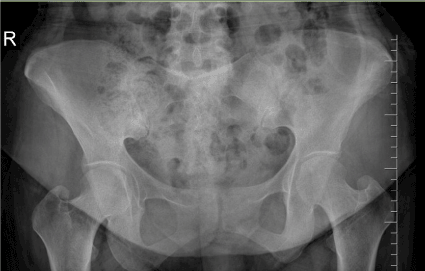

A forty-six-year-old woman was admitted to our outpatient clinic with complaints of inflammatory low back pain, widespread myalgia and knee arthritis episodes without fever that resolve spontaneously in 3-5 days. She was diagnosed with AS at age 43. Her medical history revealed mitral valvereplacement at 30 years of age due to rheumatic fever at 14 years of age. She had afamily history of FMF. On physical examination, she has not peripheral arthritis. Lumbar spinal motion was minimally limited. Sacroiliac provocation tests were positive. Chest expansion was normal. Her laboratory exam showed CRP 26 mg/L; ESR 22 mm/h. HLA B27 was negative. SAA was 3.02 mg/dl. Urine examination showed proteinuria. Genetic analysis confirmed aheterozygousmutationforM680I in theMEFVgene. X-rays indicated squaring of the lumbar vertebrae, and bilateral grade 2 sacroiliitis (Figure 1 and 2). She met diagnostic criteria for incomplete form of FMF [2]. She also met the criteria of ASAS [5]. We considered that it may be FMF spondylitis rather than the coexistence of AS and FMF. She received colchicum 0.5 mg three times daily. AFR, proteinuria and SAA were found to be normal.

Figure 2. Sacroiliac joint radiography of the patient demonstrating bilateral sacroiliitis